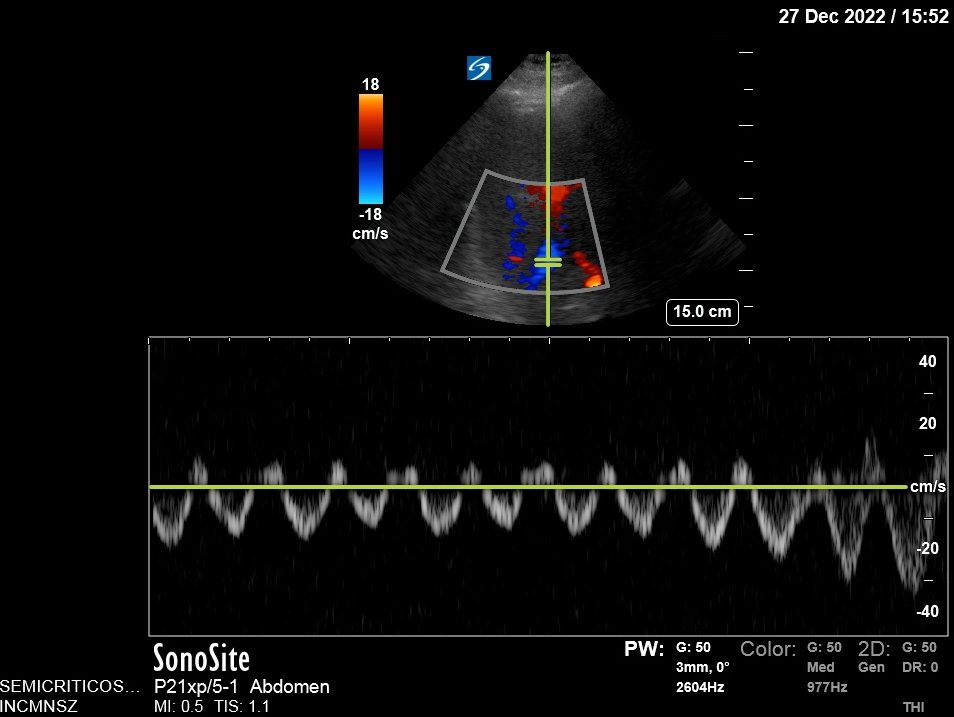

Plethoric IVC, Portal Pulsatility 39%.

However, liver congestion got worse: Portal Vein Pulsatility now 62%. This is not good, especially since LFTs came back ⬆️⬆️⬆️

Portal Vein is no longer pulsatile